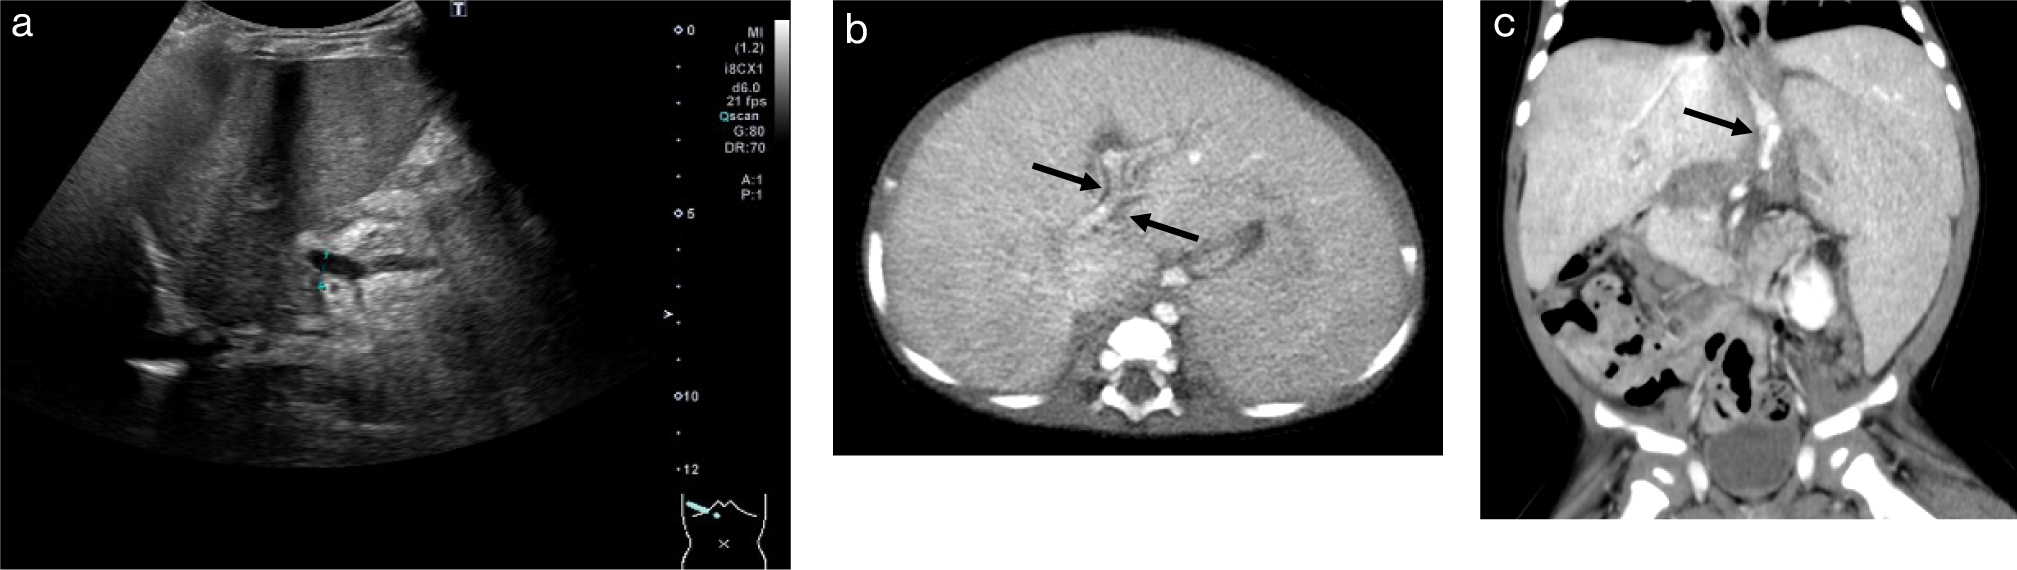

1. 胆道閉鎖症胆道閉鎖症は,新生児から乳児期早期に発症する炎症に伴って胆管組織の線維化がおこり閉塞をきたし難治性の胆汁うっ滞を呈する疾患である.小児肝移植のうちで最も頻度が高い病態である.胆道閉鎖症の治療の第1選択は,葛西手術(肝門部空腸吻合術)であるが,その後の遷延する黄疸,反復性の胆管炎,門脈圧亢進症状(難治性腹水,食道静脈瘤,肝肺症候群,脾機能亢進症状),肺高血圧症状などが見られた場合に肝移植の適応となる3,6–8).繰り返す胆管炎の症例では,肝内にbile lakeと言われる嚢胞構造を認めることが多い(Fig. 1).胆道閉鎖症に伴う門脈圧亢進症の原因の多くは,門脈狭小化と血流減弱の関与が大きい.門脈本幹の狭細化は,移植の適応判断に関与するため,普段のUSなどで注目すべきである.また,門脈圧亢進症状に伴う胃食道静脈瘤や直腸周囲の静脈瘤,脾腎シャントの情報は,術前のプランニングに必要である6)(Fig. 2).

造影CT:脾腫を認める.肝右葉に嚢胞病変あり,bile lakeと考えられる(矢印).

a.腹部US,右肋間走査:門脈本幹径の狭小化を認める.

b.腹部造影CT:肝脾腫を認める.肝実質の造影効果は不均質で,門脈周囲は低吸収である(矢印).

c.腹部造影CT冠状断像:脾腫を認める.胃噴門部に沿って側副路を認める(矢印).